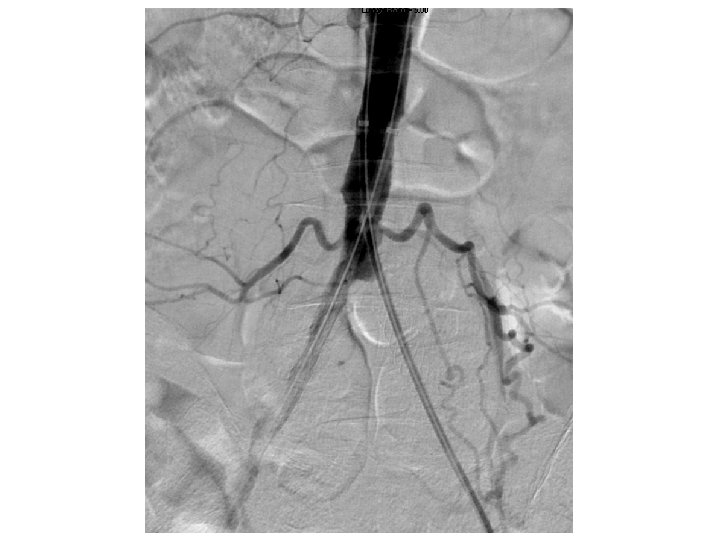

Kissing CBE Stents Still Essential With Distal Aorta Disease • In cases of aortic reentry—kissing stents insure both CIA have adequate flow • The farther the stents extend into the aorta (more that just touching) the more likely they are to narrow/occlude • Kissing Iliac stents should be BE CS (CS>>BMS) Sabri SS, et al. Outcomes of covered kissing stent placement compared with bare metal stent placement in the treatment of atherosclerotic occlusive disease at the aortic bifurcation. J Vasc Interv Radiol. 2010 Jul; 21(7): 995 -1003.

Single Versus Kissing Stents for Unilateral Proximal CIA Disease • Unilateral >50% CIA and 30%-50% in the contralateral CIA • 80 patients (69 males, 66. 6 years) treated with a single stent and 30 (26 males, 67. 1 years) treated with kissing stents • Two patients in the single-stent group (3%) required bailout kissing stents because of plaque shift to the contralateral side • Major complication rates: 8% in single-stent vs 13% in the kissing -stent group (P =. 399) • At 3 years, the single-stent and kissing-stents group had similar primary patency (89% vs 87%; P =. 916) and target lesion revascularization-free survival (93% vs 87%; P =. 462) Suh Y et al. Outcomes of the single-stent versus kissing-stents technique in asymmetric complex aortoiliac bifurcation lesions. J Vasc Surg. 2015; 62: 68 -74